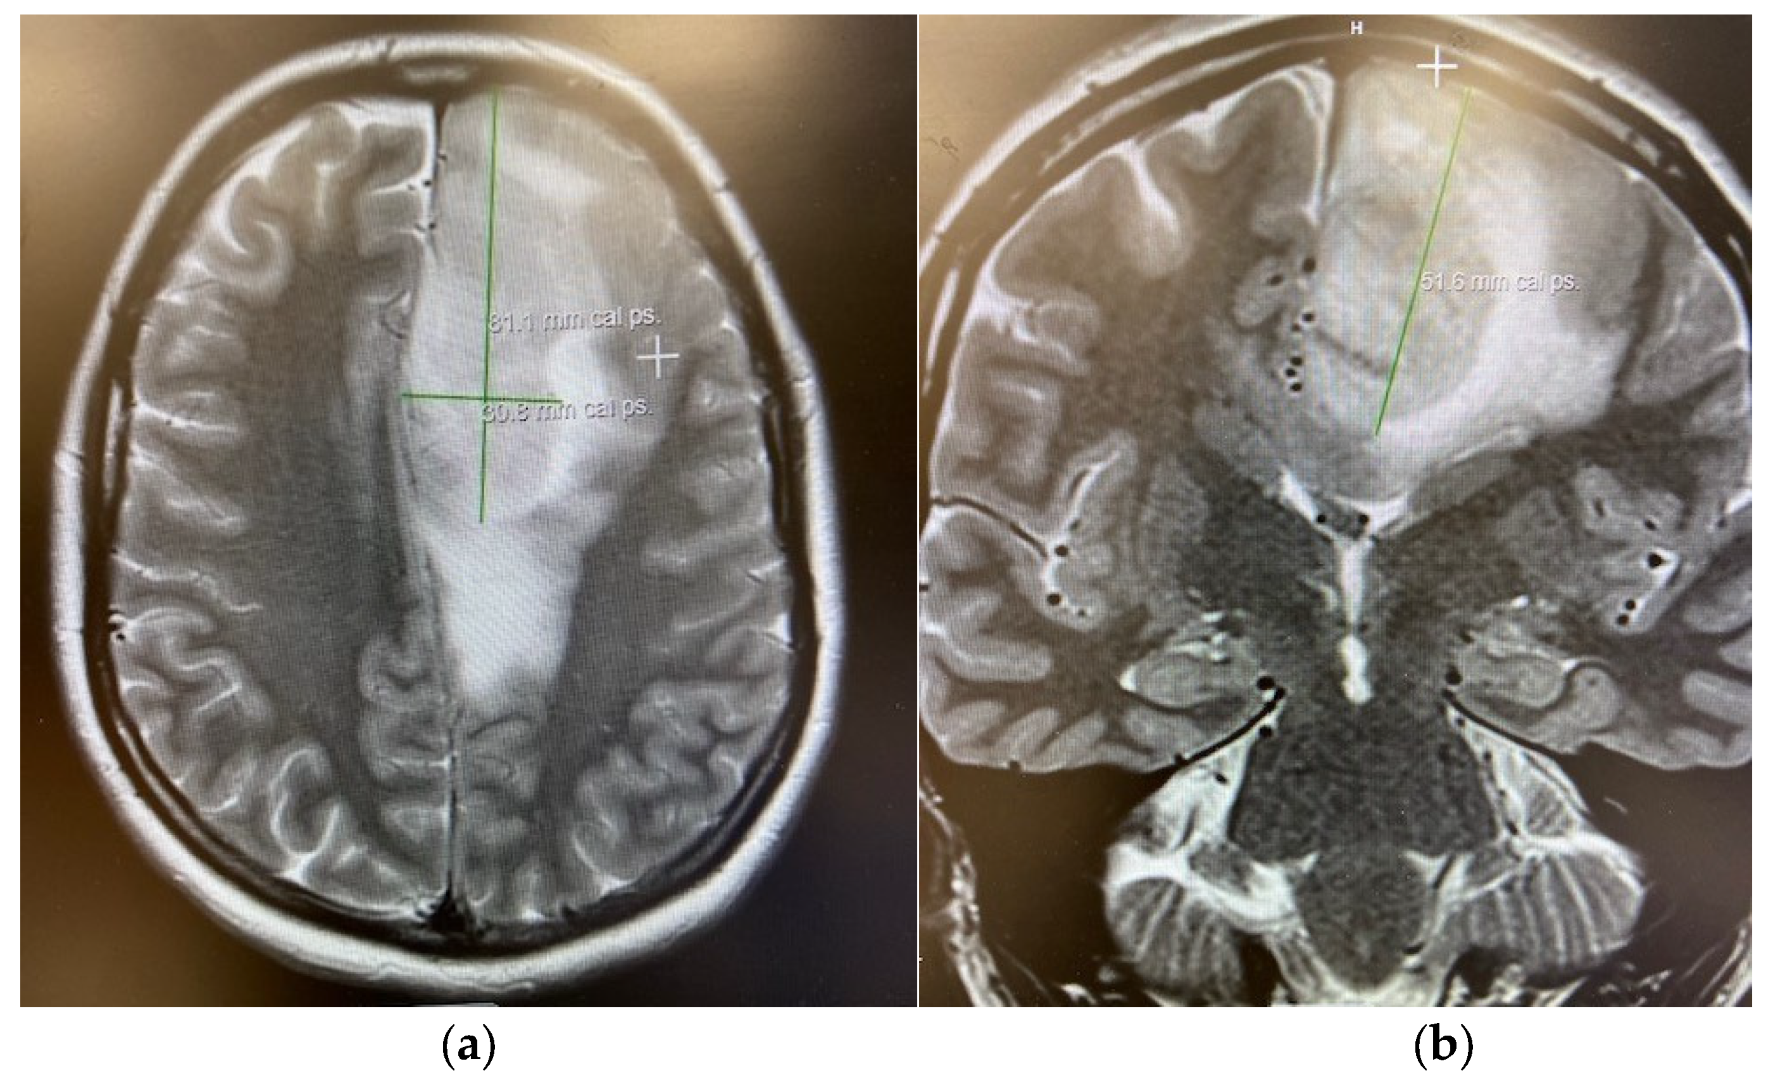

| Mellinghoff et al., 2021 [11] | Vorasidenib | n = 52 (Oligo = 16) (22 non-enh; 30 enh) | 36.8 mo (non-enh); 3.6 mo (enh) | NR | ORR: 18.2% (non-enh); 0% (enh) | non-enh: 90.9%; enh: 56.7% | Phase I | Non-enhancing tumors had better outcomes. |

| Mellinghoff et al., 2020 [12] | Ivosidenib | n = 66 total (Oligo ≥ 3) (35 non-enh; 31 enh) | 13.6 mo (non-enh); 1.4 mo (enh) | NR | 2.9% (non-enh) 0% (enh) | 88.6% (non-enh) 45.2% (enh) | Phase I | Non-enhancing tumors had better outcomes. |